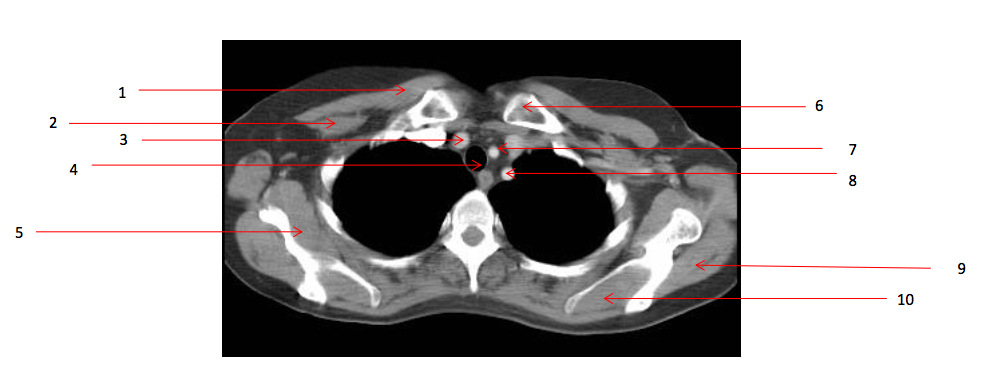

Number 2?

Rt pectoralis minor muscle

Number 6?

Lt clavicle

Number 1?

Rt pectoralis major muscle

Number 8?

Lt subclavian artery

Number 4?

Trachea

Number 7?

Lt common carotid artery

Number 5?

Rt subscapularis muscle

Number 9?

Lt infraspinatus muscle

Number 3?

Brachiocephalic artery